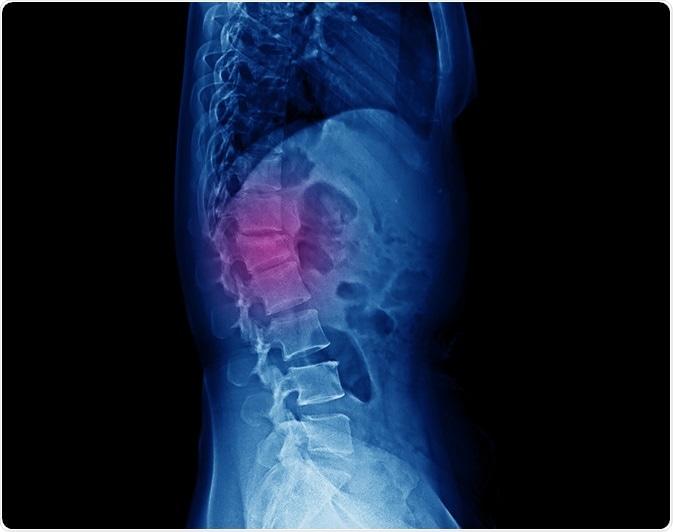

Lateral projection lumbar spine x-ray showing compression fracture at L1 vertebra with mild degree height loss. Image Credit: Yok_onepiece / Shutterstock